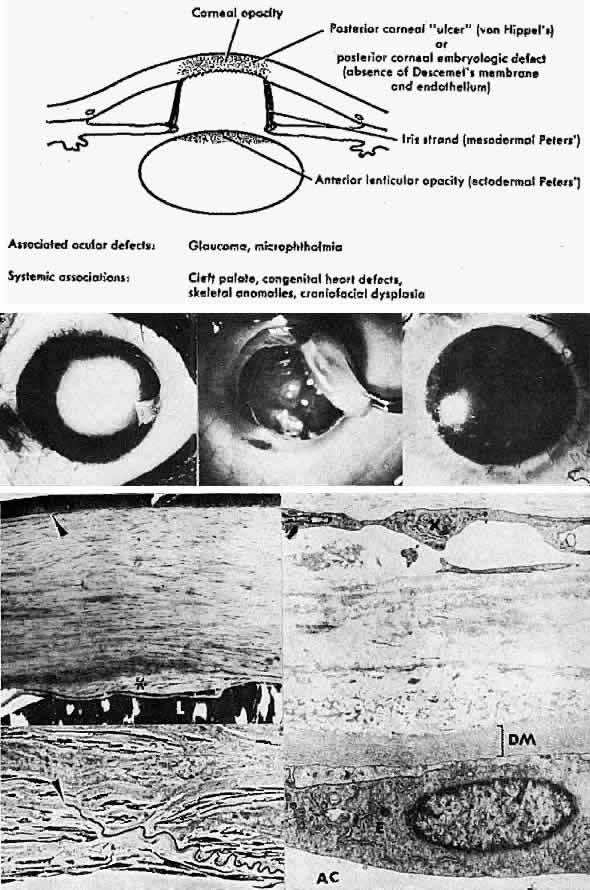

Plana, p 505. London, Kimpton, 1963 15. Kolkott W: Cornea plana und Mikrocornea periplana. Klin Monatsbl Augenheilkd 98:372, 1937 16. Reese AB, Ellsworth RM: The anterior chamber cleavage syndrome. Arch Ophthalmol 75:307, 1966 17. Kenyon, KR: Mesenchymal dysgeneses of the cornea. Metab Ophthalmol 2: 173, 1978 18. Waring GO, Bourne WM, Edelhauser HF et al: The corneal endothelium: Normal and pathologic structure and function. Ophthalmology 89:531, 1982 19. Townsend WM, Font RL, Zimmerman LE: Congenital corneal leukomas. II. Histopathologic findings in 19 eyes with

central defect in Descemet's membrane. Am J Ophthalmol 77:192, 1974 20. Townsend WM, Font RL, Zimmerman LE: Congenital corneal leukomas. III Histopathologic findings in 13 eyes with

noncentral defect in Descemet's membrane. Am J Ophthalmol 77:400, 1974 21. Bahn CF, Falls HF, Varley GA: Classification of corneal endothelial disorders based on neural crest origin. Ophthalmology 91:558, 1984 22. Kenyon KR: Mesenchymal dysgenesis in Peters' anomaly, sclerocornea and congenital

endothelial dystrophy. Exp Eye Res 21:125, 1975 23. Waring GO III, Rodrigues MM, Laibson PR: Anterior chamber cleavage syndrome: A stepladder classification. Surv Ophthalmol 20:3, 1975 24. Axenfeld T: Embryotoxon corneae posterius. Dtsch Ophthalmol Gesamte 42:301, 1920 25. Sugar HS: Juvenile glaucoma with Axenfeld's syndrome: A histologic report. Am J Ophthalmol 59:1012, 1965 26. Dark AJ, Kirkham TH: Congenital corneal opacities in a patient with Rieger's anomaly and